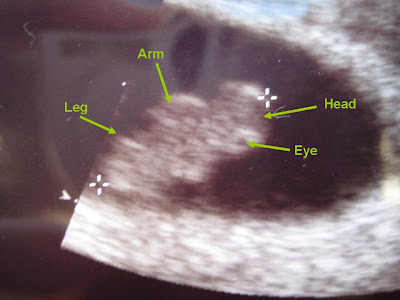

I don't post much on the Houston board, but I lurk :-) Wanted to share my good news from my appt yesterday. I'm going to Baylor Clinic and had a great 1st experience. I thought I'd get a choice of hospitals since my OB is affiliated with Women's, St. Luke's, and Methodist, but the info packet I got just says the practice delivers at St. Luke's. If anyone has info regarding this, I'd appreciate it. It's too early for me to worry about right now, though. :-) Love lurking on your convos, ladies!

From Baby pictures

• Cute little gummy bear!